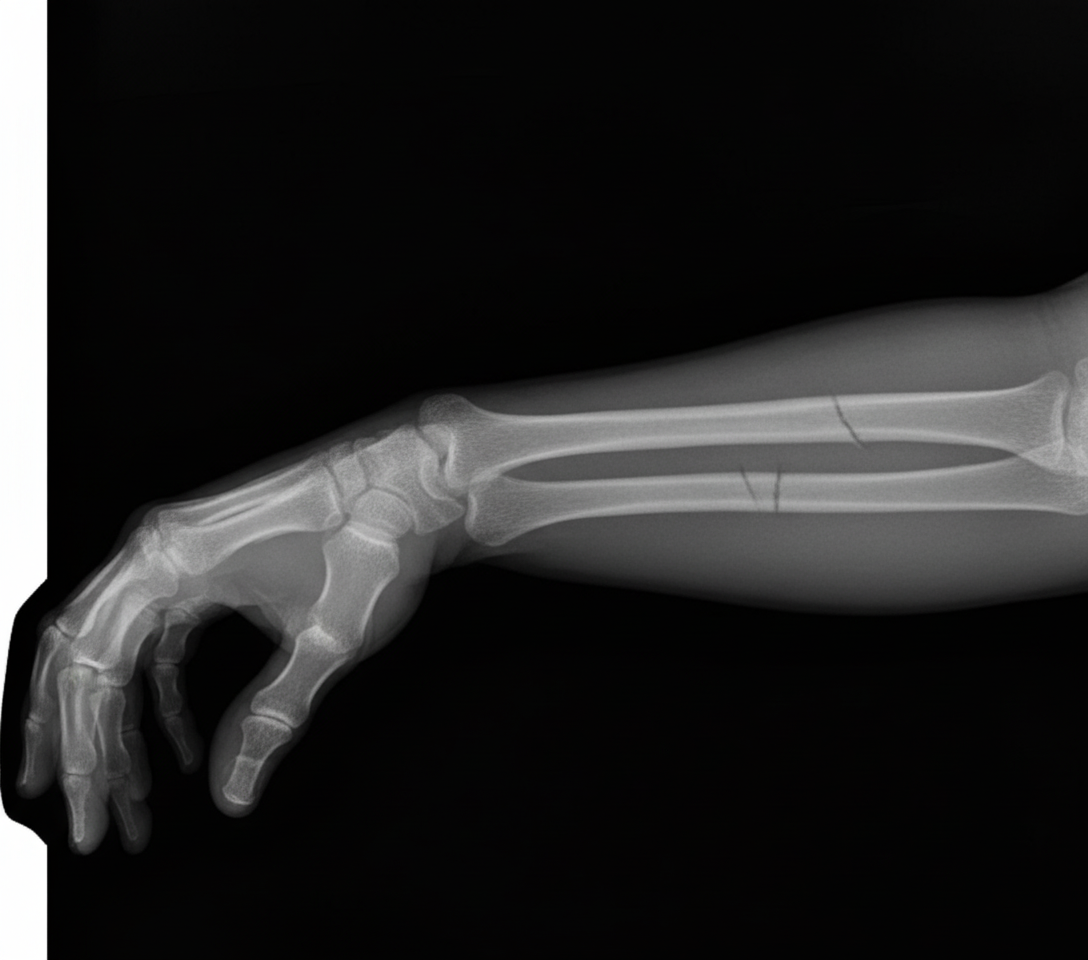

The provided X-ray shows a fracture of which bone?

Explanation: ***Both Radius and Ulna*** - **Both-bone forearm fractures** typically occur from high-energy trauma such as falls or motor vehicle accidents, causing fractures of both the **radius** and **ulna** shafts. - X-ray shows clear fracture lines through both bones, which is distinct from isolated fractures like **Monteggia** (ulna fracture with radial head dislocation) or **Galeazzi** (radius fracture with distal radioulnar joint disruption). *Radius* - An isolated **radius fracture** would show fracture line only through the radius bone while the **ulna remains intact**. - Should be accompanied by **distal radioulnar joint disruption** (Galeazzi fracture) if truly isolated, which requires careful evaluation of joint alignment. *Ulna* - An isolated **ulna fracture** would demonstrate fracture through the ulna shaft with an **intact radius**. - Often associated with **radial head dislocation** (Monteggia fracture), requiring assessment of the **radiocapitellar line** on lateral views. *None of the above* - The X-ray clearly demonstrates **fracture lines** through both forearm bones, making this option incorrect. - **Both-bone forearm fractures** are common injuries requiring surgical fixation due to the **interosseous membrane** disruption and potential for **compartment syndrome**.